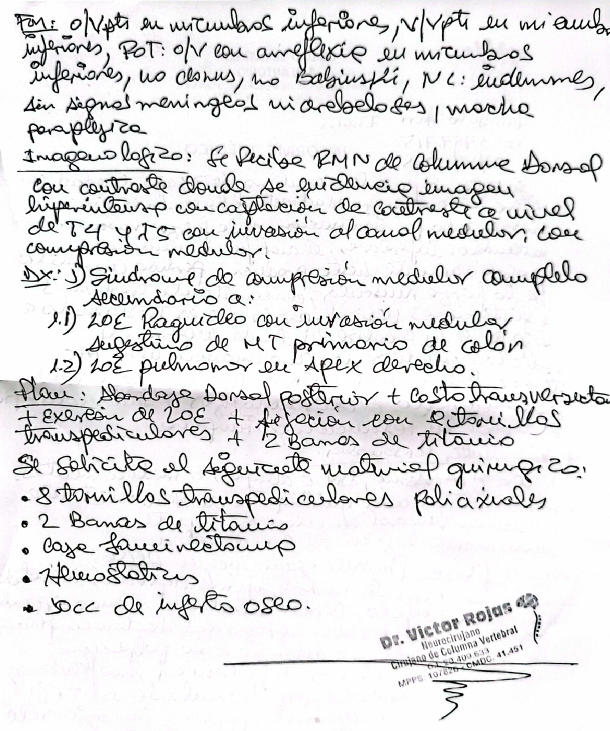

Examen físico: Paciente consciente, con parálisis en ambas piernas (paraplejía), reflejos ausentes en miembros inferiores, alteración de esfínteres, pero sin signos meníngeos ni cerebelosos.

Estudios de imágenes: Resonancia magnética de columna dorsal: se observa una lesión tumoral que invade el canal medular, causando compresión de la médula espinal a nivel de las vértebras T4 y T5.

Diagnóstico: Síndrome de compresión medular completo, secundario a: Metástasis ósea de cáncer de colon con invasión medular. Metástasis pulmonar en ápice derecho.

Plan terapéutico: Cirugía propuesta: Abordaje dorsal posterior con fijación mediante tornillos transpediculares (8 tornillos poli-axiales). Colocación de 2 barras de titanio y caja intersomática.Exéresis (retiro) de la lesión tumoral. Pleurostomía (drenaje pleural). Estudio anatomopatológico de tejido óseo obtenido.